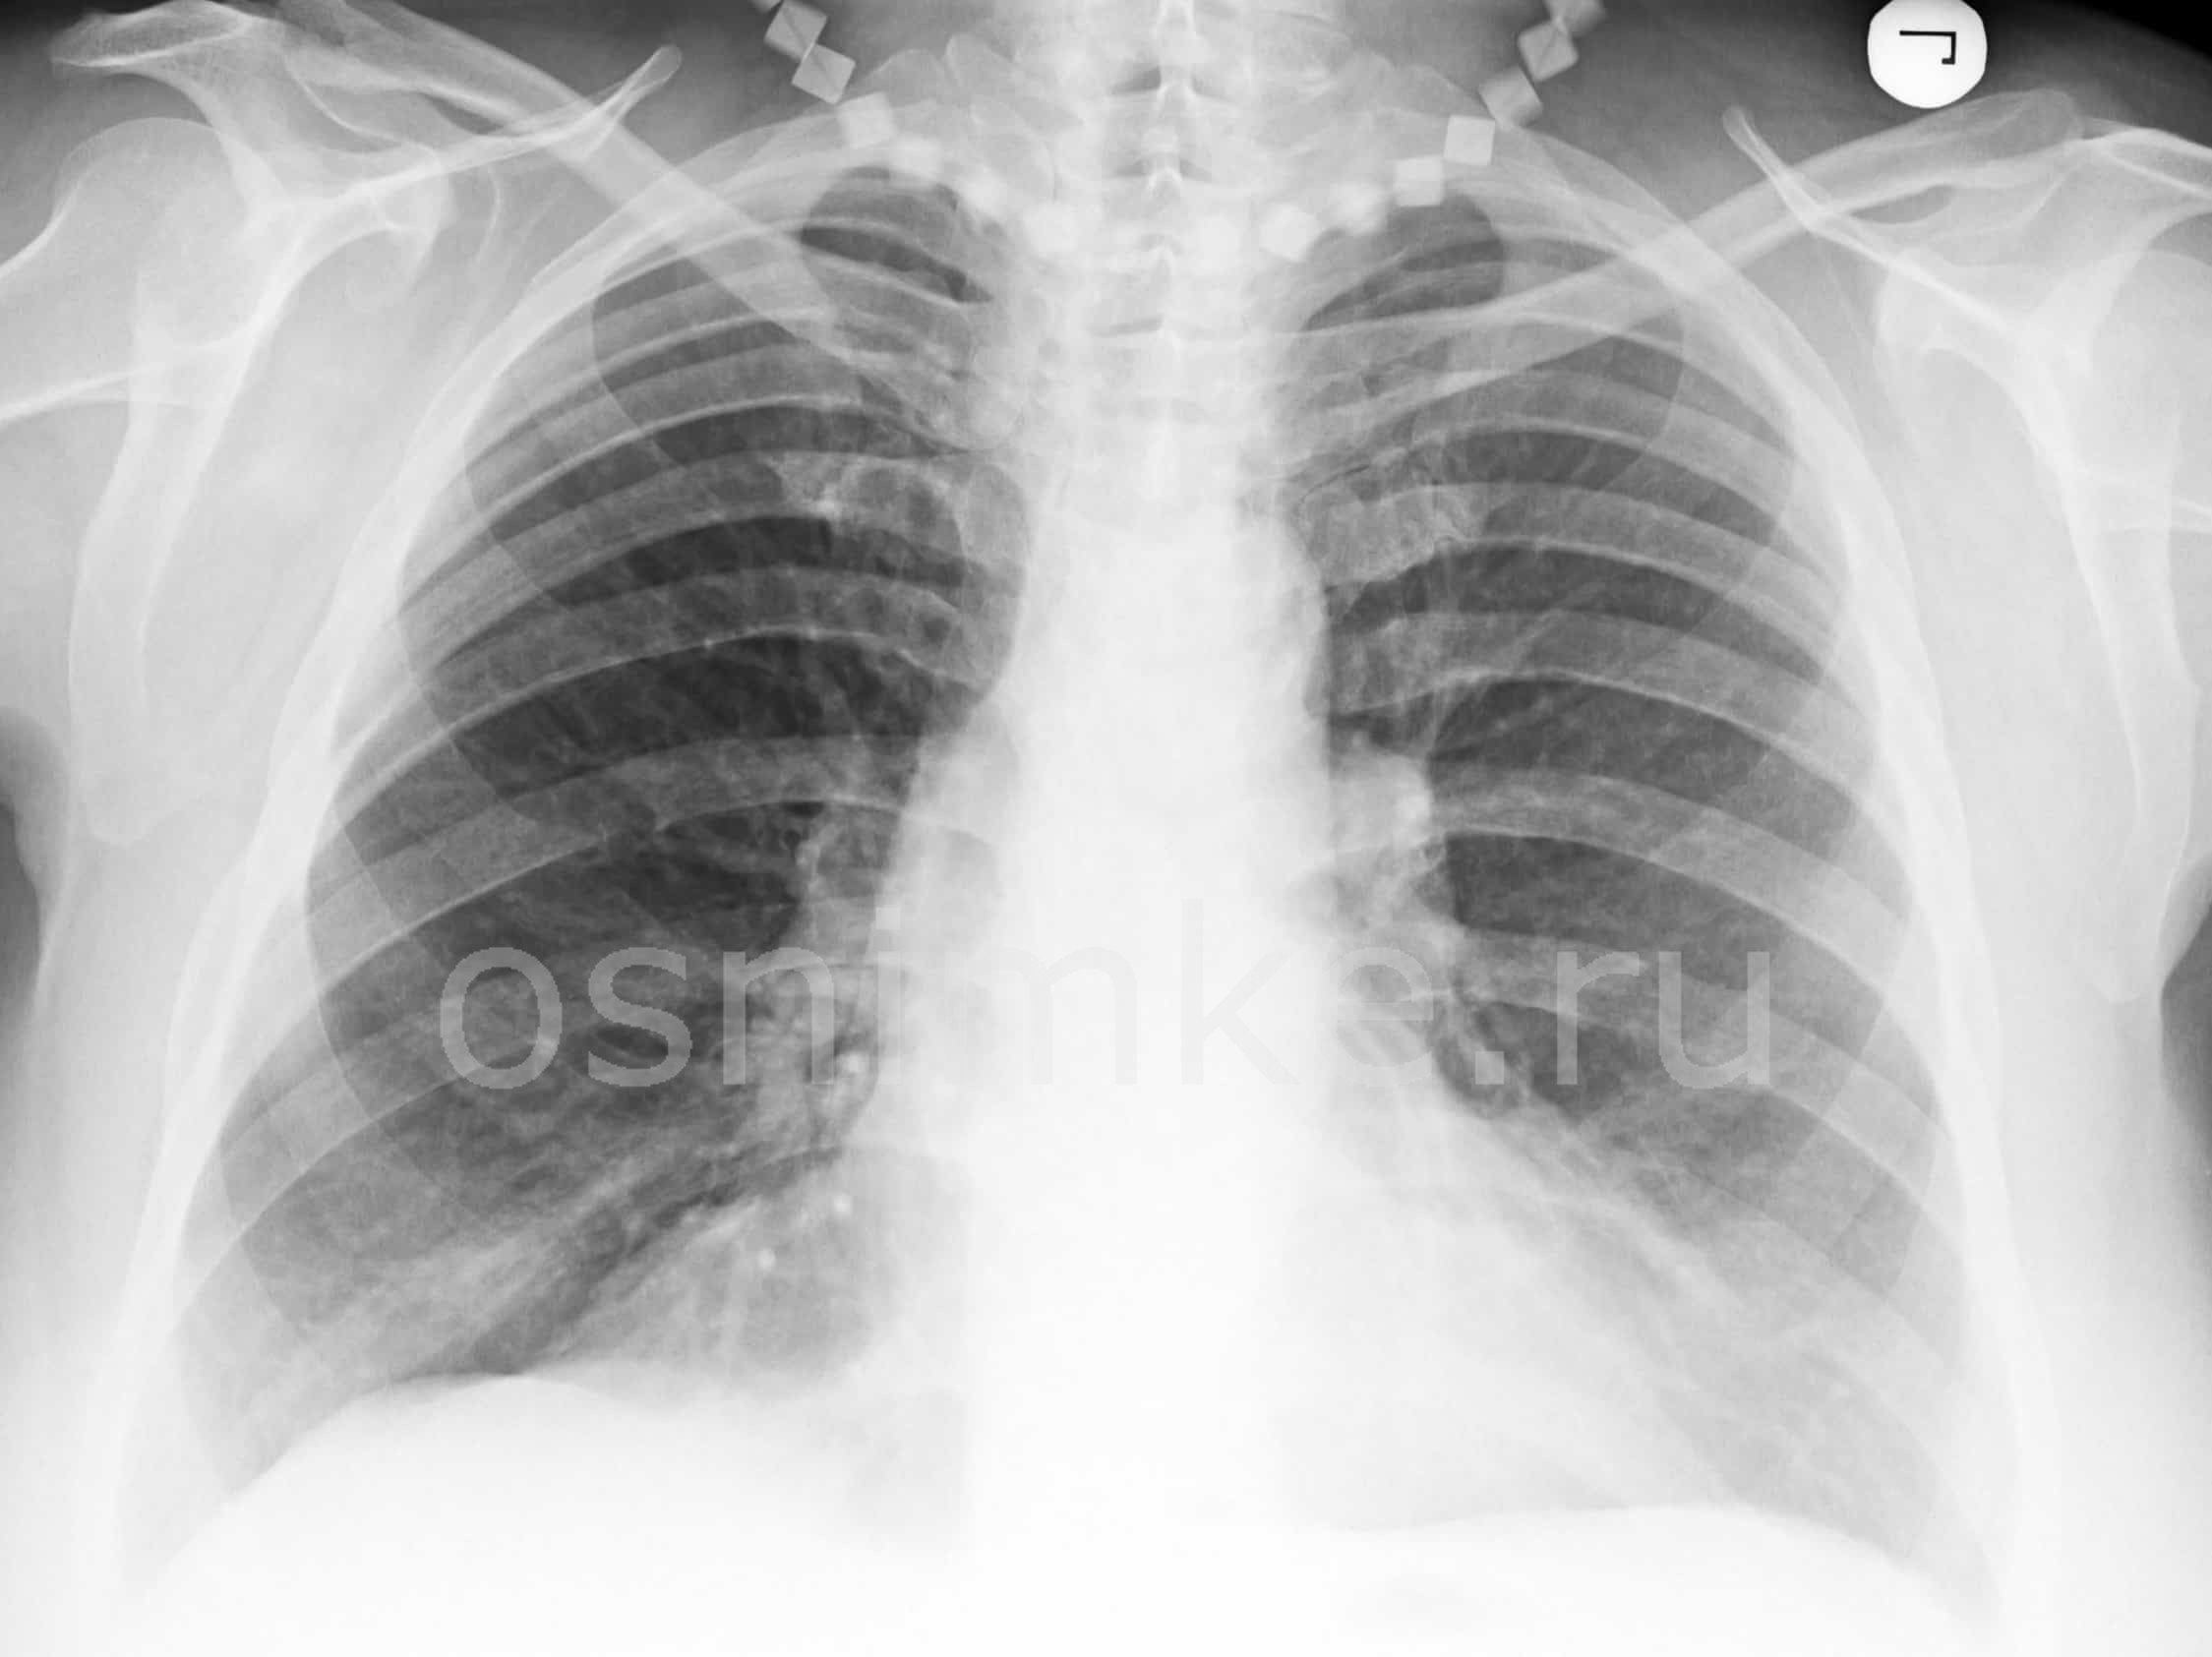

Атипичная пневмония на рентгеновском снимке:

При атипичной пневмонии легких на рентгеновском снимке видны затемнения:

- мелкоочаговые – не более 3 мм;

- среднеочаговые – не более 7 мм;

- крупноочаговые – не более 12 мм;

- фокусные – более 12 мм.